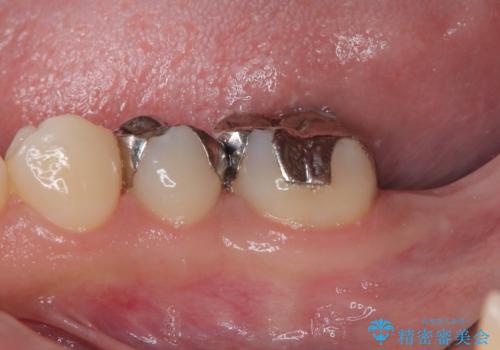

- 奥歯を抜歯してから放置しているとのことで来院された患者様です。

歯が割れて抜歯になってしまったとのことで、咬合力に抵抗できるよう、インプラントによる補綴治療を行うこととしました。

長い期間歯が欠損していた下顎奥歯に、インプラント埋入と同時に仮歯を装着すると(埋入即時荷重インプラントを行うと)、舌の付け根で仮歯を横向きに押してしまい、インプラントが脱落する危険性が高くなります。

インプラント埋入時に、装着できる状態の仮歯を用意するものの、埋入後すぐには加重させず、インプラントが無事に生着したことを確認した後に装着することで、危険を回避しつつ外科処置や痛みの少ないスムーズな治療を行うことができます。